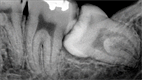

Alternatives to Root Canal

Root Canal